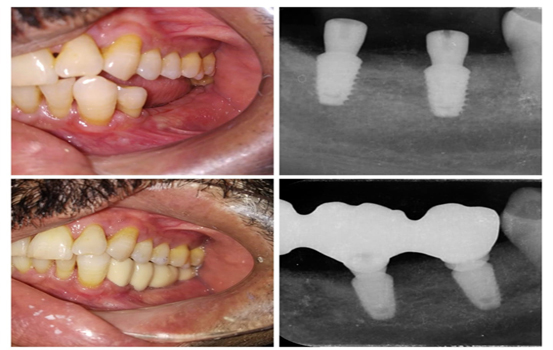

2) Two Dental Implants

If you have multiple missing teeth in the posterior region of the jaw (upper or lower), typically two implants are placed in that area. These two implants can support the replacement of three to four teeth, including the implants themselves, depending on the condition of the bone and the level of oral hygiene in that region.

In the anterior region of the jaw, whether in the upper or lower front teeth area, two implants can be placed to support the replacement of up to five teeth, including the implants. This is contingent upon the condition of the bone and the health of the remaining teeth, which are assessed through X-rays and a review of the patient’s medical history.

In the anterior region of the jaw, whether in the upper or lower front teeth area, two implants can be placed to support the replacement of up to five teeth, including the implants. This is contingent upon the condition of the bone and the health of the remaining teeth, which are assessed through X-rays and a review of the patient’s medical history.